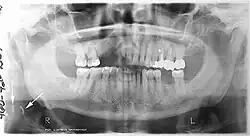

A dental panoramic radiograph, showing the maxilla and mandible, all the teeth including the "wisdom teeth," the frontal and maxillary sinuses, the nasal cavity and the temporomandibular joint and other near by head and neck anatomy. | |

A panoramic radiograph is a panoramic scanning dental X-ray of the upper and lower jaw. It shows a two-dimensional view of a half-circle from ear to ear. Panoramic radiography is a form of focal plane tomography; thus, images of multiple planes are taken to make up the composite panoramic image, where the maxilla and mandible are in the focal trough and the structures that are superficial and deep to the trough are blurred.